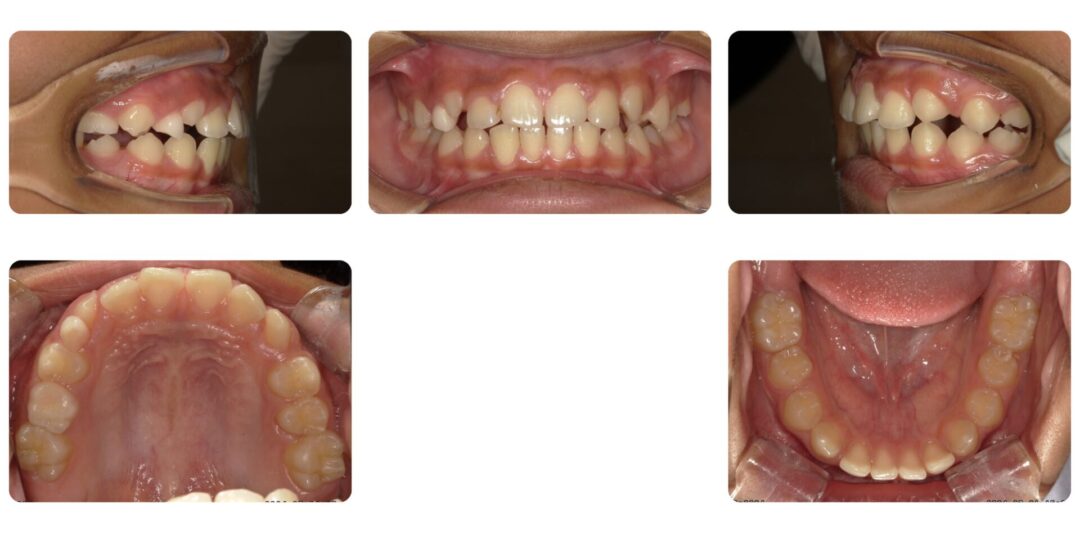

過蓋咬合を伴う骨格性上顎前突|初診時10歳

矯正治療前

ご相談内容

上前歯がスカスカ、前突感

治療内容

第一期治療 拡大ネジ付きバイオネーターによる歯列矯正

治療期間

1年5ヶ月